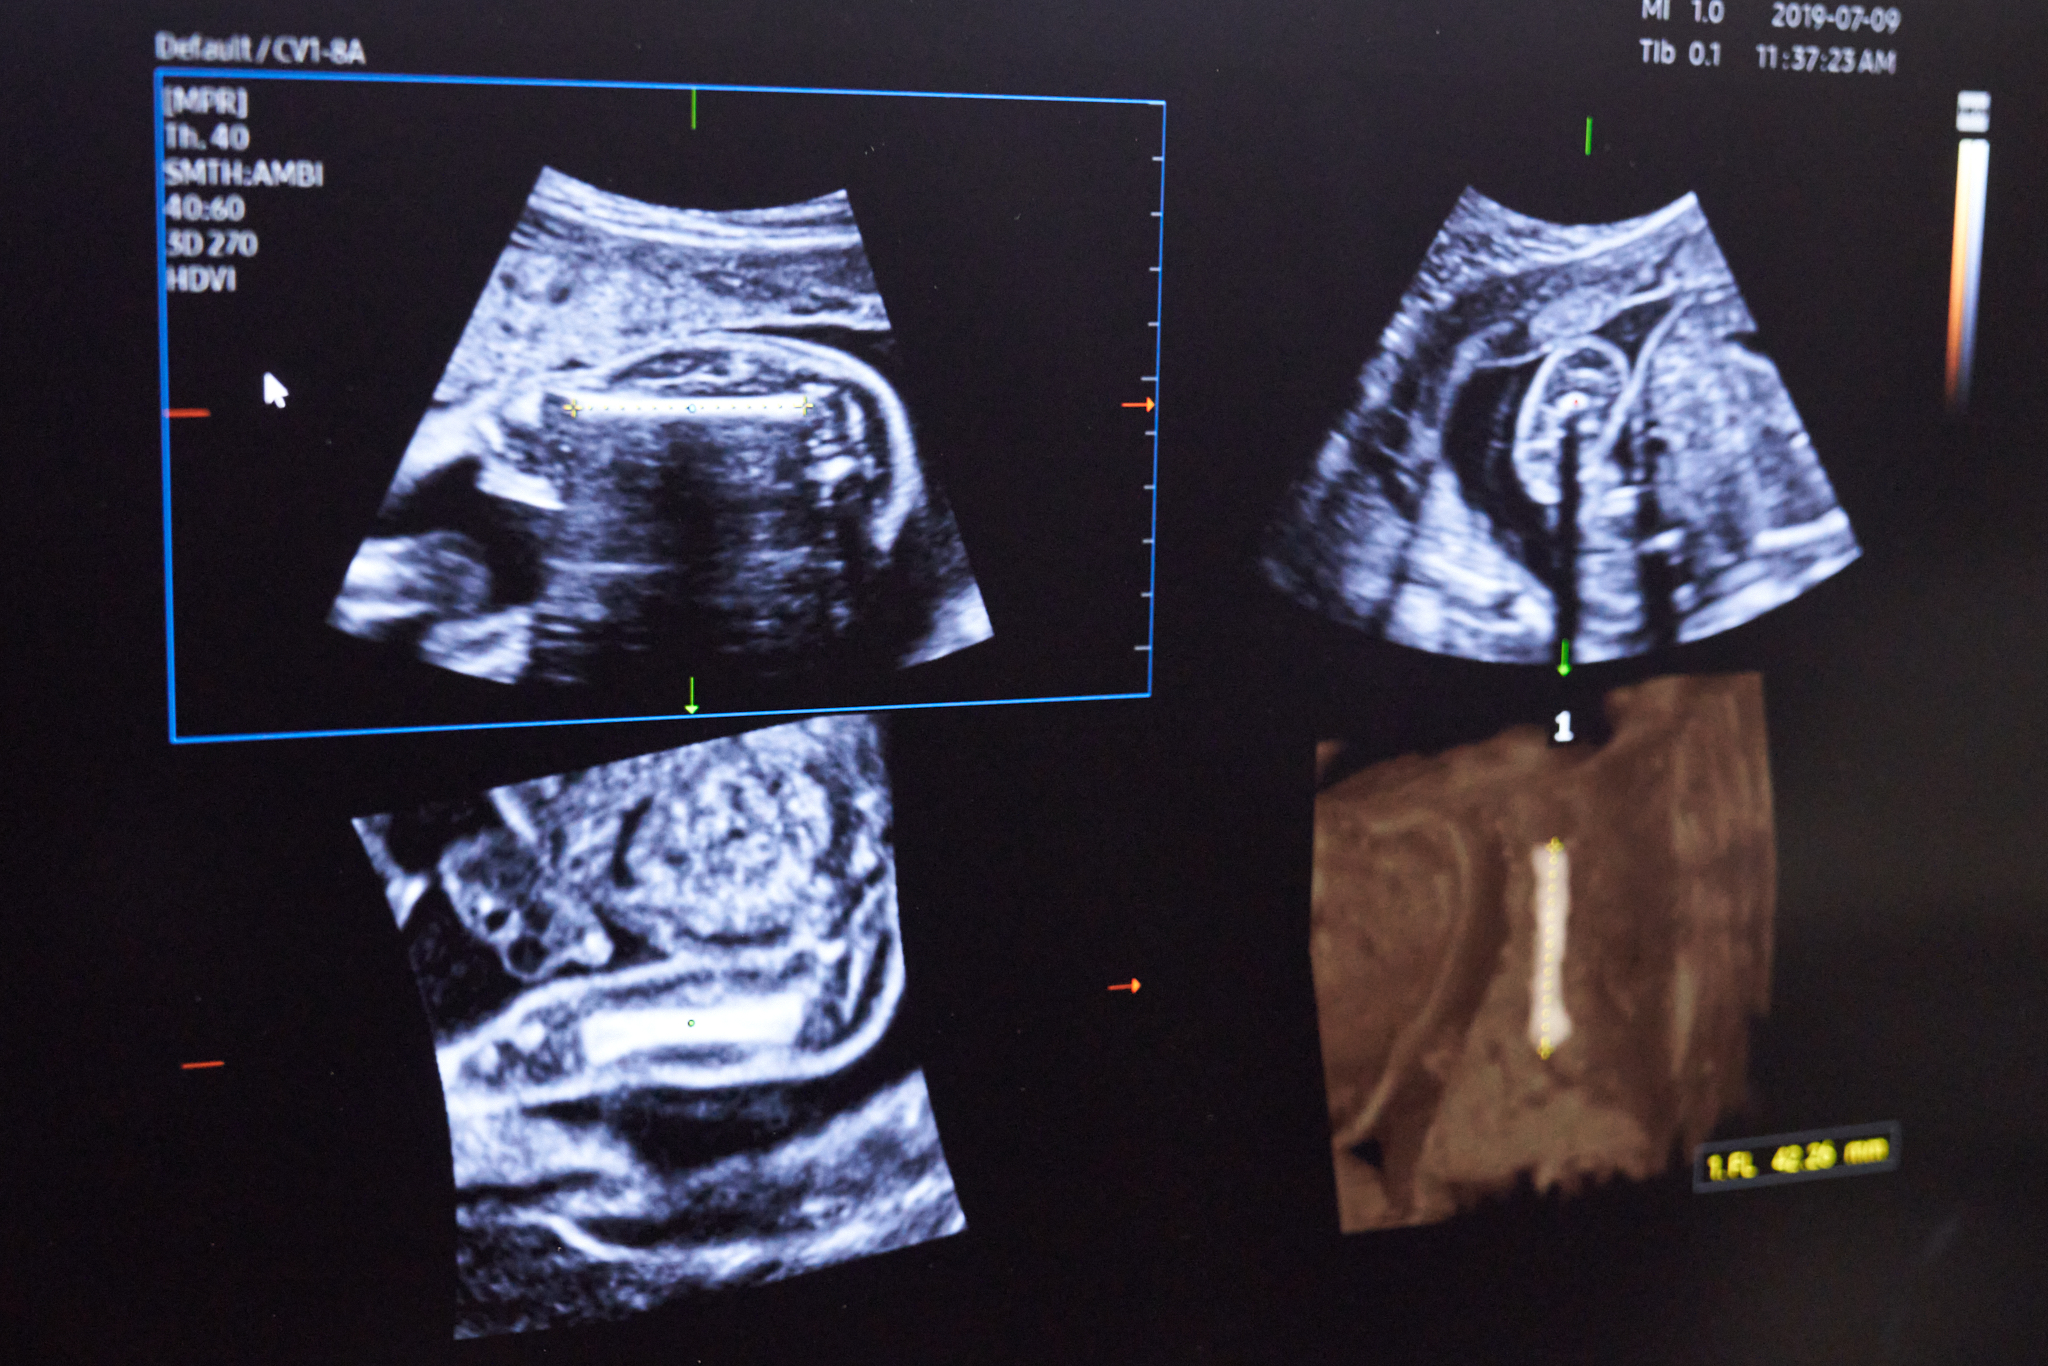

По информации областного минздрава, в 2023-2024 годах в регионе внедрили пять медицинских изделий с ИИ для анализа снимков: для маммографии, флюорографии, рентгенографии и КТ органов грудной клетки, а также КТ головного мозга. Ошибки алгоритмов, как заверяют чиновники, составляют не более 3%.